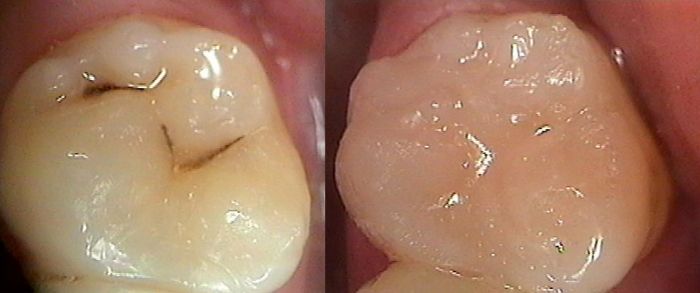

What should I know about early detection & treatment of tooth decay?

At the slightest hint of tooth decay I use a tooth decay detection dye. This dye is placed on the supsect area of the tooth. After rinsing the area with water any active decay present is stained bright pink. At this point I can treat the area appropriately. The end result is removal of the active decay & restoration of the area with a strong, long lasting, nearly invisible, mercury free, tooth coloured composite resin filling.